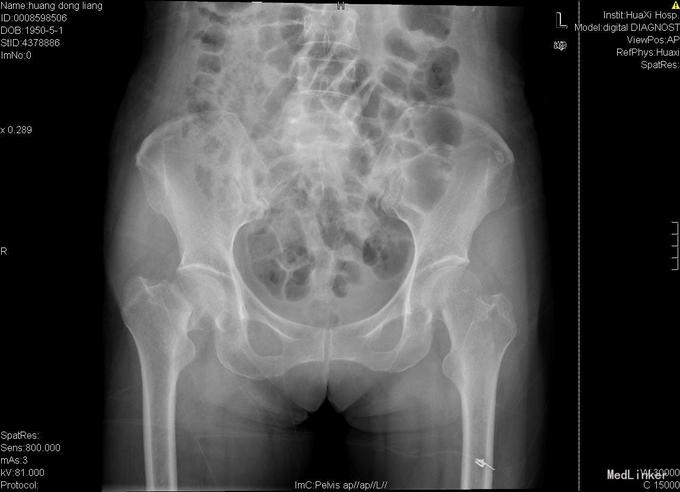

患者女,70岁,因"摔伤后右髋部疼痛、活动障碍10小时"入院,患者诉10小时前在家不慎滑倒,当即感觉右髋部疼痛、活动障碍,于当地医院急诊检查示:右股骨颈骨折,为求进一步诊疗故来我院。

查体:右髋部略水肿,右髋关节活动受限,不能负重。右髋部压痛(+),纵向叩击痛(+)。右髋关节活动受限,右膝及踝、足趾诸关节活动正常。 辅查:X线片示右股骨颈骨折,断端分离、错位。

入院诊断:右股骨颈骨折 诊疗计划:择期手术治疗,行右侧全髋关节置换。